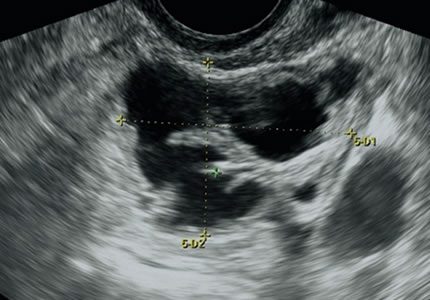

Comprehensive pelvic ultrasound evaluations for a wide range of non-pregnancy female health concerns, symptoms, or referrals.

Routine & Diagnostic Gynaecological Scans